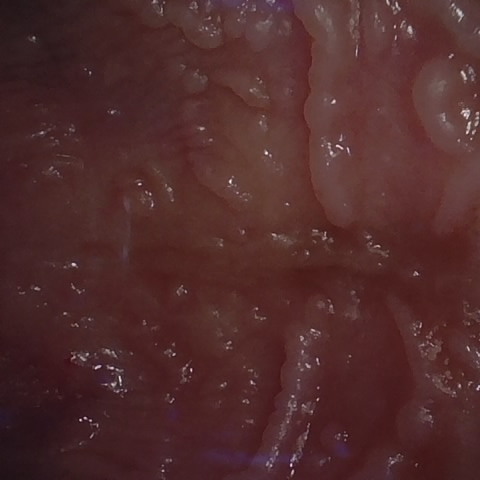

NHD39174

Annotated as "Good"